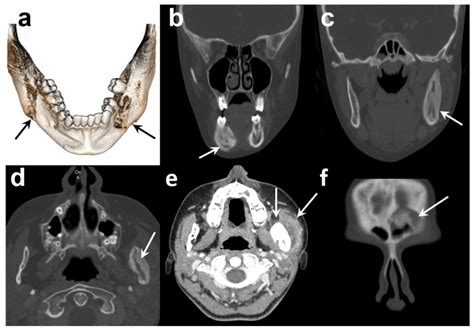

When you visit a dentist or an oral surgeon, they will perform a physical examination to check for tender areas, redness, and swelling. However, a clinical exam is rarely enough to confirm a diagnosis. Professionals typically rely on imaging and laboratory tests to confirm a jaw bone infection.

Diagnostic Tool Purpose

X-rays To identify bone changes or large abscesses.

CT Scan Provides detailed 3D views of the bone structure.

MRI Excellent for detecting soft tissue inflammation.

Blood Tests To check for elevated white blood cell counts (signs of infection).

Biopsy/Culture To identify the specific bacteria causing the infection.